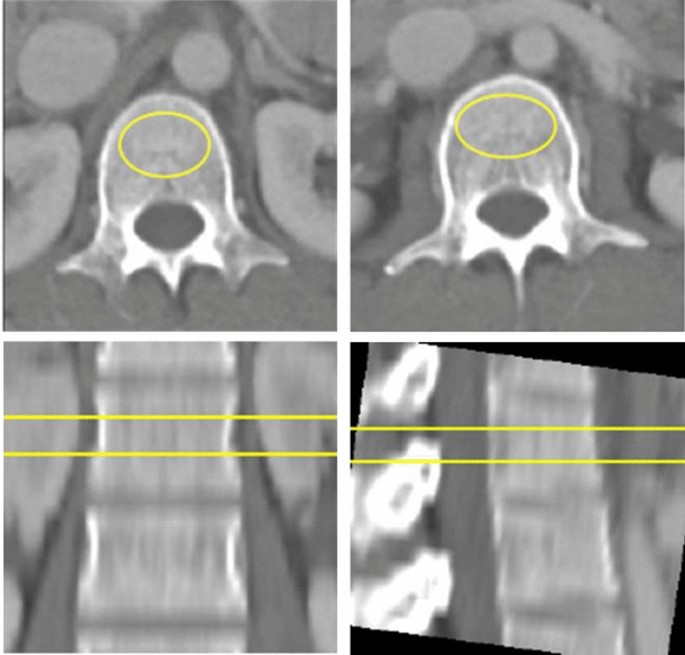

Quantitative CT (QCT) is an advanced imaging test that uses a CT scanner to measure bone mineral density (BMD). Unlike traditional bone density scans (DEXA scans), QCT creates a 3D view of the bone and can measure the soft, inner part of the bone (trabecular bone) separately from the hardest outer shell (cortical bone). This makes it easer to detect early changes in bone strength related to age, disease, or treatment. QCT can be performed in mere minutes taking less time out of your busy day.

QCT provides highly accurate and sensitive bone density measurements because it uses volumetric 3D imaging. This allows it to distinguish different bone types and detect early bone loss more effectively than traditional DXA scans. QCT results are also less affected by factors that can distort DXA readings, such as body fat, arthritis, or calcifications.